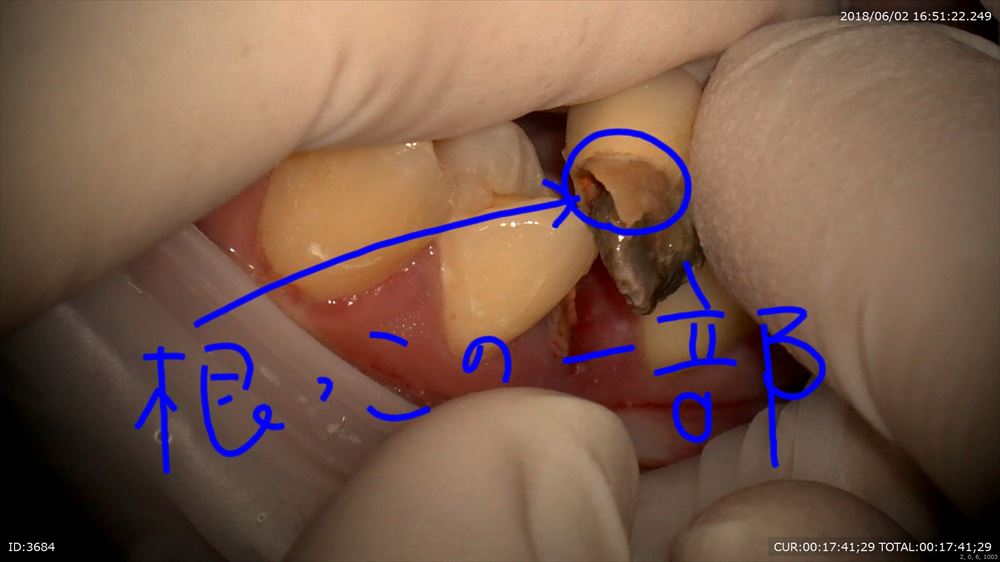

この方は他院で抜歯といわれ納得いかず来院。

マイクロスコープは動画で説明できるメリットがあります。

歯根破折なので私の診断も抜歯でした。

きちんと動画で説明。

揺れている原因は

このように

歯根ごと折れて

2本ヒビがはいっています。